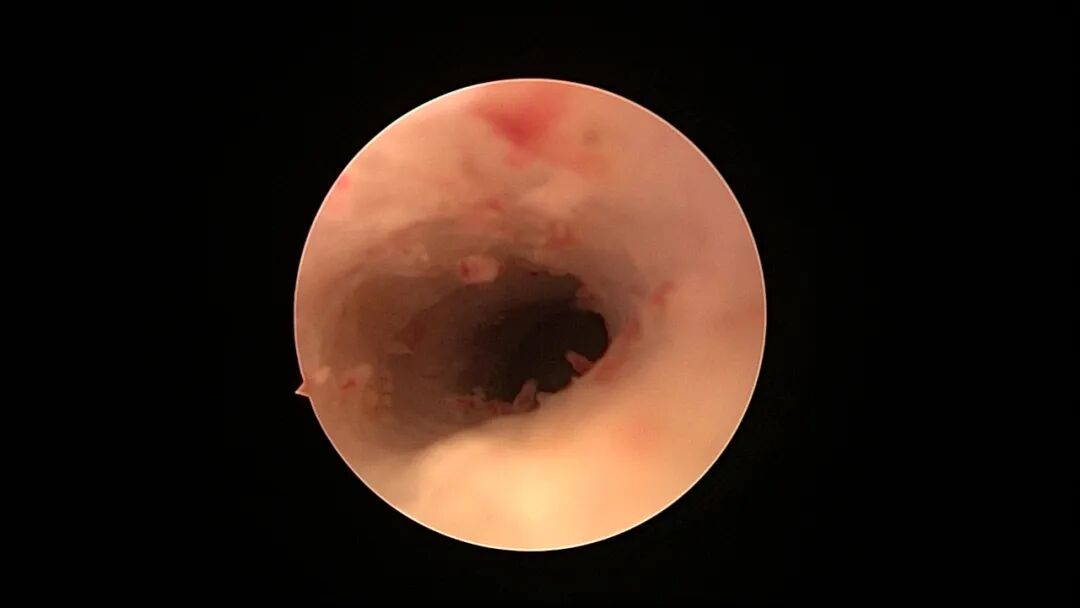

病例3:30岁,G8P1,顺产1次。月经淋漓不净10余天,月经周期第11天B超示宫腔回声宽约0.5cm,内可见絮状回声,有流动感。宫腔镜探查,宫颈管见血迹,宫腔粘连,内膜草莓状,单极电针分粘,内膜活检,病检为增殖期样子宫内膜伴出血。